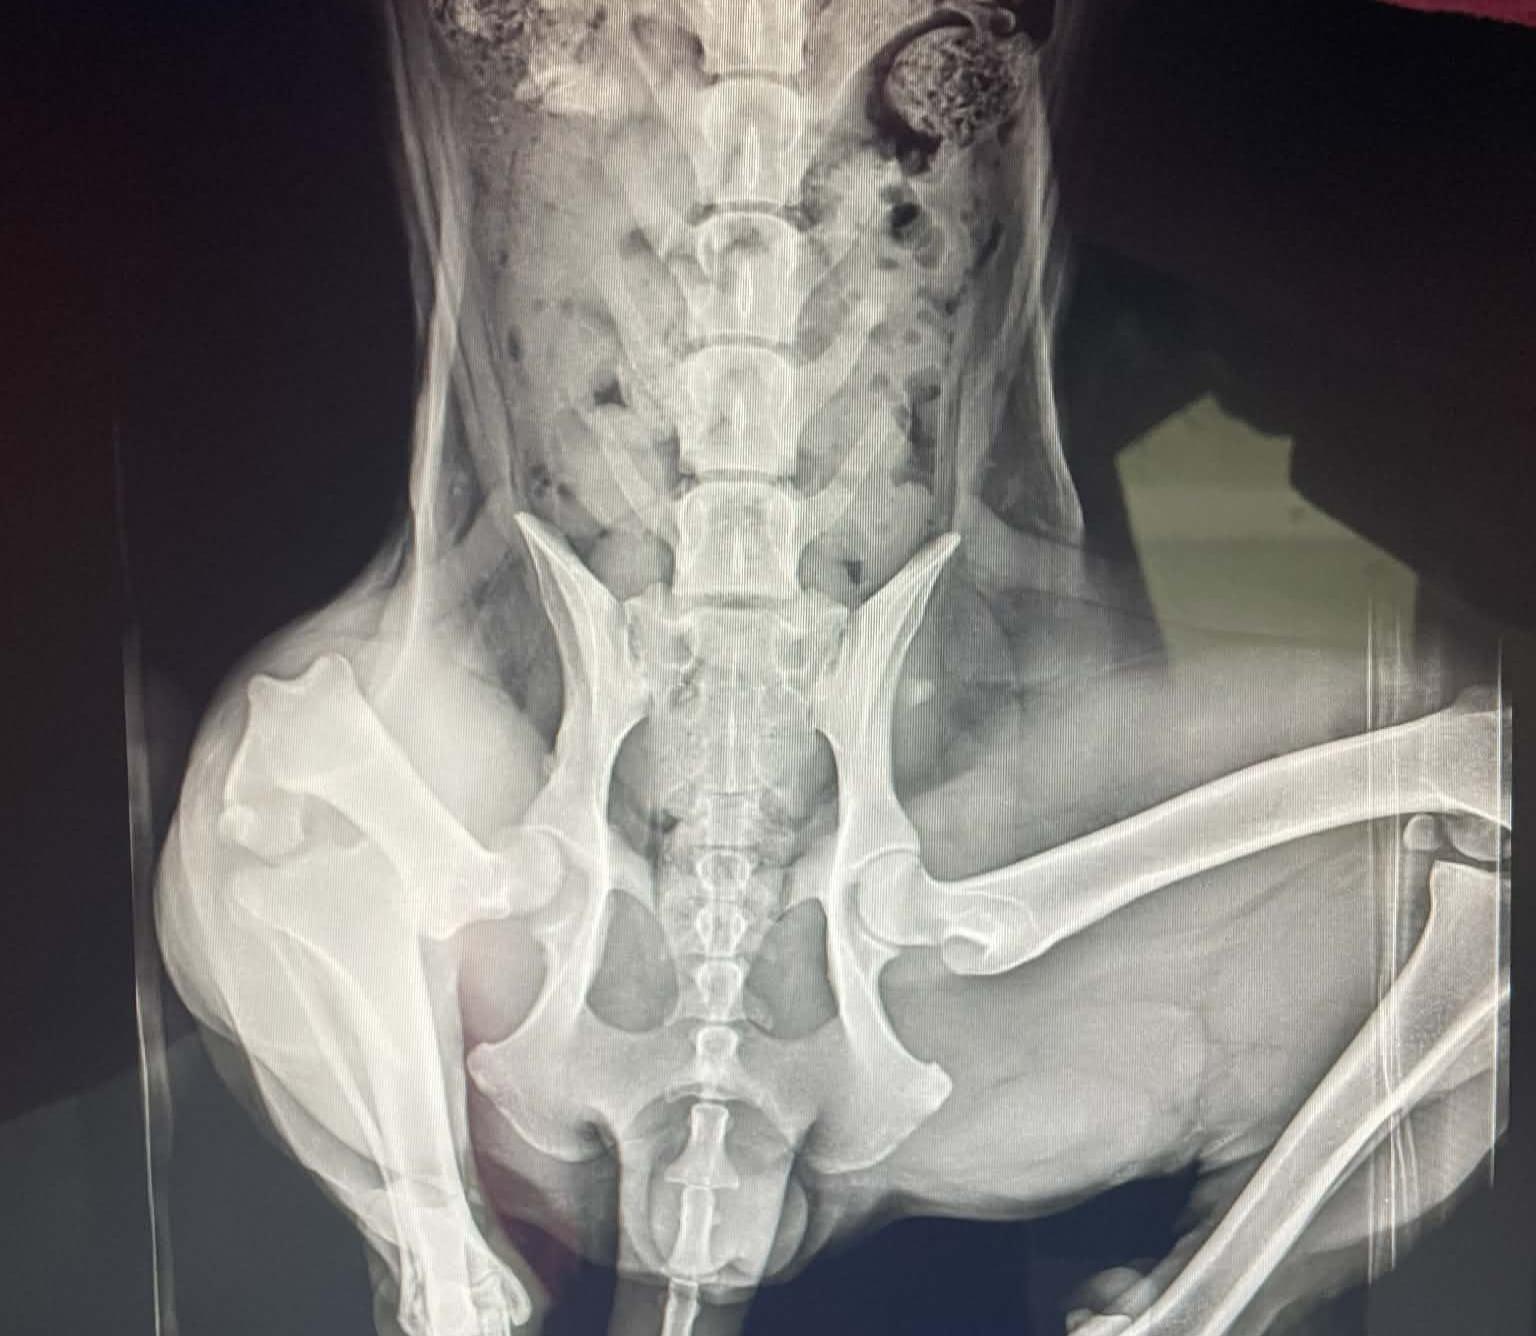

Shortly after arriving in foster care, it became clear that something wasn’t right with her leg. X-rays revealed that this sweet girl had a dislocated hip. Once she was given pain medication, Maisie immediately began playing like the puppy she truly is—showing just how much discomfort she had been living with.

Our options were amputation or an FHO (femoral head ostectomy) surgery, and we chose surgery in order to save her leg. Thanks to generous fundraising efforts and overwhelming community support, Maisie was able to receive the surgery she needed. She is still in the healing process, but we are now accepting applications for when she is ready for adoption. 🤍